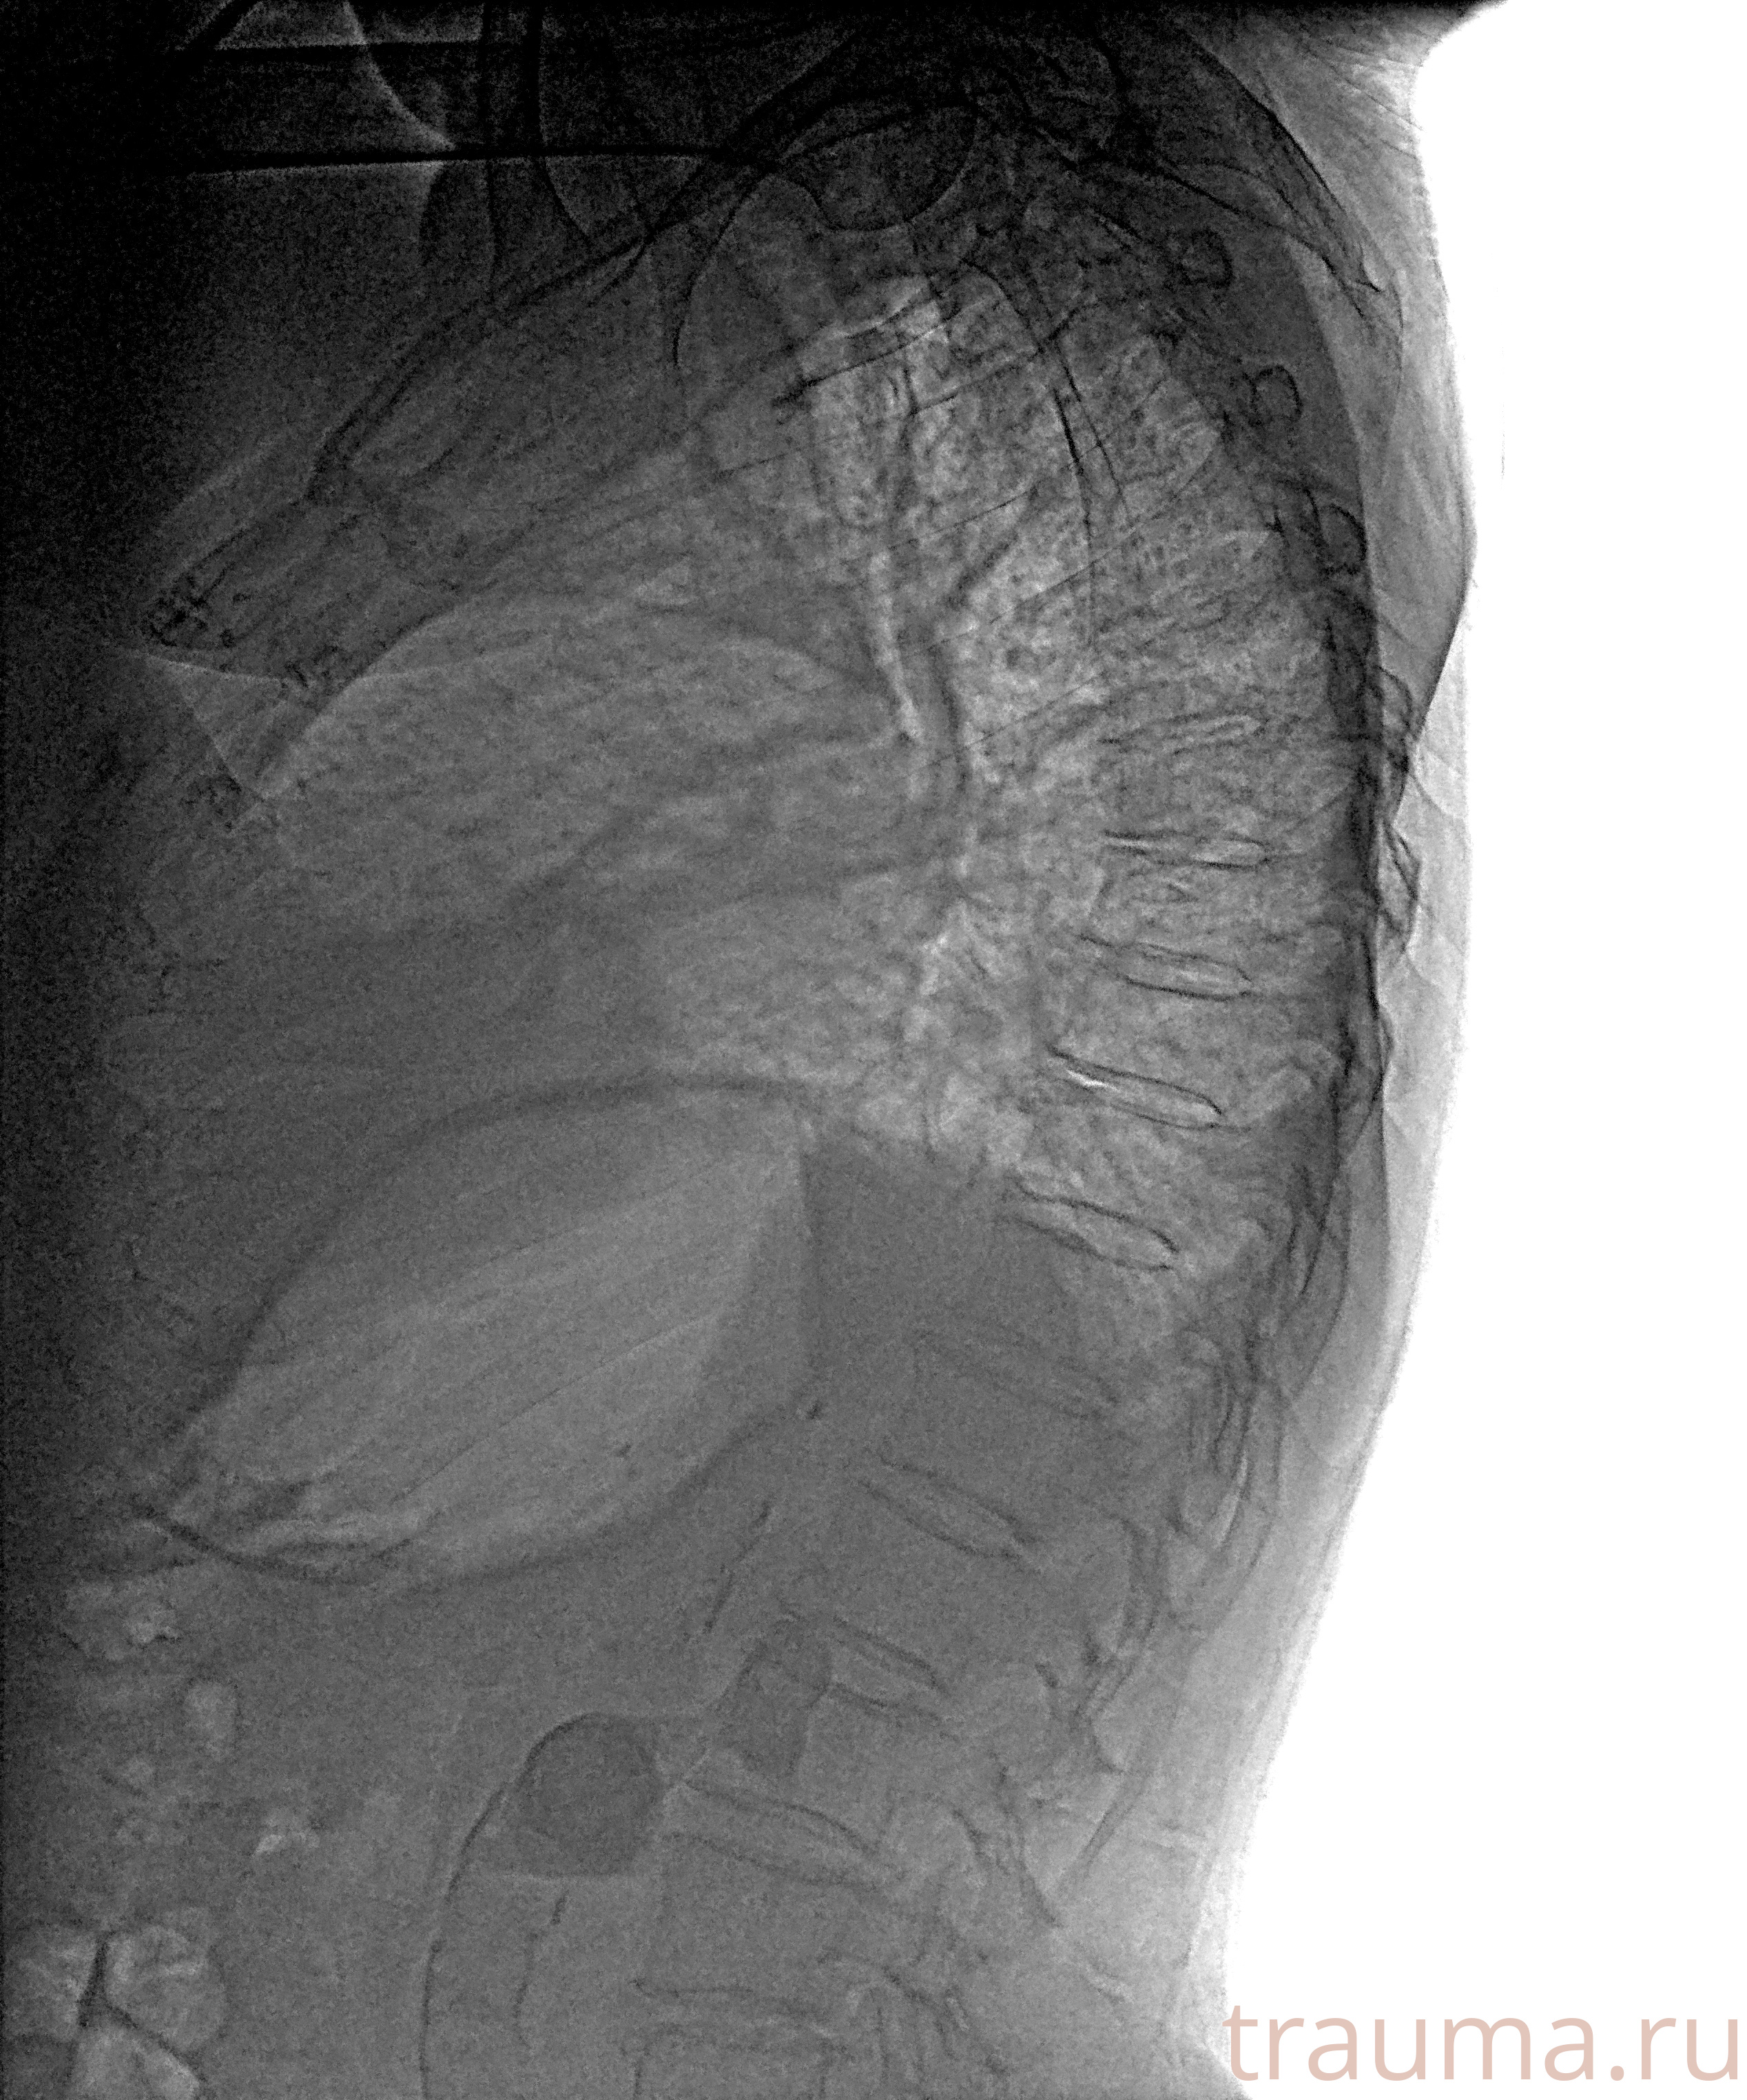

Рентгенограммы

Рентген на дому: по вашему адресу приезжает врач-рентгенолог, травматолог-ортопед с мобильным рентгеновским аппаратом, проводит диагностику травмы или заболевания, делает необходимые рентгенограммы, дает рекомендации по дальнейшему лечению. Получить качественные снимки в домашних условиях возможно благодаря уникальной методике, разработанной МосРентген Центром для института  Склифосовского